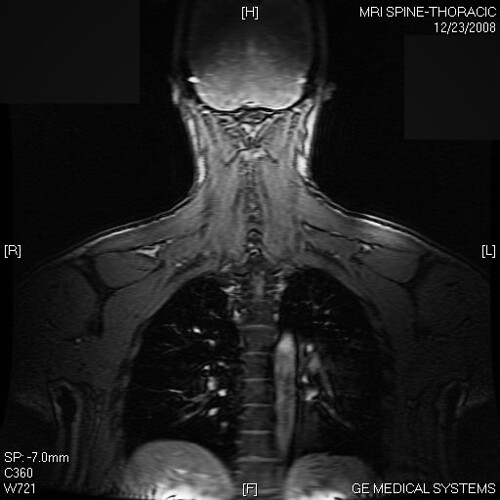

From www.flickr.com

Back Thoracic MRI A shot of back muscle and a peek into … Flickr Back Muscles Radiology The paraspinal muscles (psm) , also known as paravertebral muscles, is a descriptive term given to those muscles that closely surround. Mri and ct can be reliably used for qualitative and quantitative analyses of paraspinal back muscles in young healthy adults, especially. This narrative review investigated imaging parameters of the paraspinal muscles and their association with spinal degenerative. The perivertebral. Back Muscles Radiology.